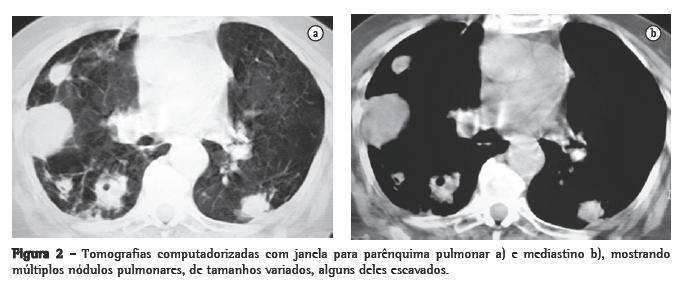

Mulher, branca, 89 anos, com DPOC e relato de bronquiectasias no lobo superior esquerdo há pelo menos 20 anos. O diagnóstico funcional de DOPC foi realizado pelo resultado da relação volume expiratório forçado no primeiro segundo/capacidade vital forçada de 41,2% após o uso de broncodilatador na prova de função pulmonar. Usava diariamente brometo de tiotrópio, b2-agonista de longa duração, associado a corticosteróide inalatório desde setembro de 2004; nas exacerbações agudas, utilizava corticosteróide sistêmico associado a antibiótico de largo espectro. Há 5 dias iniciou quadro de tosse com secreção purulenta, febre de 38 °C, sudorese noturna, prostração intensa, dispnéia e anorexia. Foi prescrito ciprofloxacina por 10 dias, sem melhora clínica, tendo sido internada por 10 dias pelo agravamento do quadro clínico. Nessa primeira internação, a radiografia de tórax mostrava espessamento de paredes brônquicas, pequenas opacidades mal definidas nos lobos superior e inferior direitos e atelectasia com bronquiectasias no lobo superior esquerdo. Foi isolada Klebsiella pneumoniae pela cultura do escarro, e prescrito ceftriaxone, piperacilina/tazobactan. Obteve alta com melhora da febre e da tosse. Em casa, houve recidiva dos sintomas com piora da dispnéia. Realizada radiografia do tórax no domicílio, com aparelho portátil, que mostrou imagens nodulares disseminadas nos pulmões, motivando uma segunda internação (Figura 1). Ao exame apresentava fácies de sofrimento; prostrada; hipocorada; taquipnéica (44 ciclos/min); ­taquicárdica (120 bpm); temperatura axilar, 37 °C; pressão arterial, 120/80 mmHg; e saturação periférica de oxigênio, 84% em ar ambiente. Roncos em ambos os pulmões.

Inicialmente foi prescrita a associação sulfametoxazol e trimetoprima, sem resposta clínica. Foram então prescritas amicacina associada a Imipenem/cilastatina por 15 dias, com excelente resposta clínica e radiológica (Figura 1). Recebeu alta hospitalar com prescrição de sulfametoxazol e trimetoprima por mais 8 semanas.

A apresentação radiológica torácica é inespecífica. Os achados radiológicos mais comuns são as consolidações e os grandes nódulos irregulares.

Nódulos, massas escavadas, derrame pleural, pneumotórax, opacidades em vidro fosco e padrões intersticiais podem também ocorrer.(1,4,5,11) Alguns estudos mostram que, em pacientes HIV positivos, existe um percentual maior de lesões escavadas.(8) A consolidação alveolar nos lobos superiores é muitas vezes confundida com tuberculose pulmonar.(6) Embora as alterações vistas na TC sejam ­semelhantes às das radiografias convencionais, a TC é superior na demonstração da exata localização e extensão das lesões, assim como na diferenciação entre lesões pulmonares e pleurais.(5) No caso relatado, a paciente apresentava imagens nodulares de tamanhos variados, disseminadas por ambos os pulmões, e algumas delas escavadas.